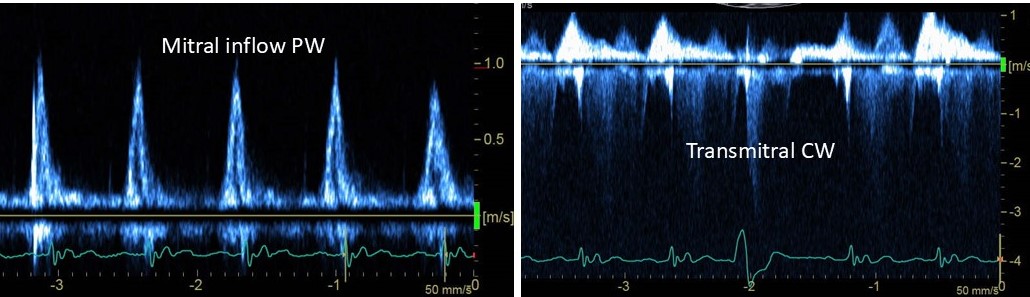

An elderly patient with known severe left ventricular dysfunction is admitted with hypotension. Annular tissue Doppler velocities are low. What are the likely left ventricular filling pressures?